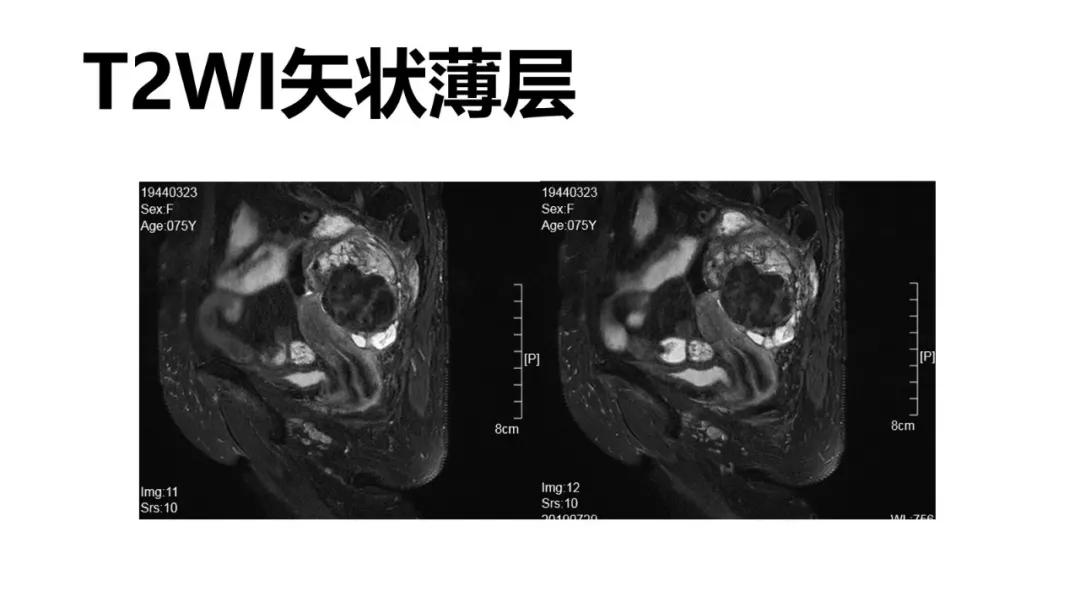

- T2WI抑脂低信号:卵泡膜细胞瘤、纤维瘤

病理:左侧卵巢卵泡膜-纤维瘤